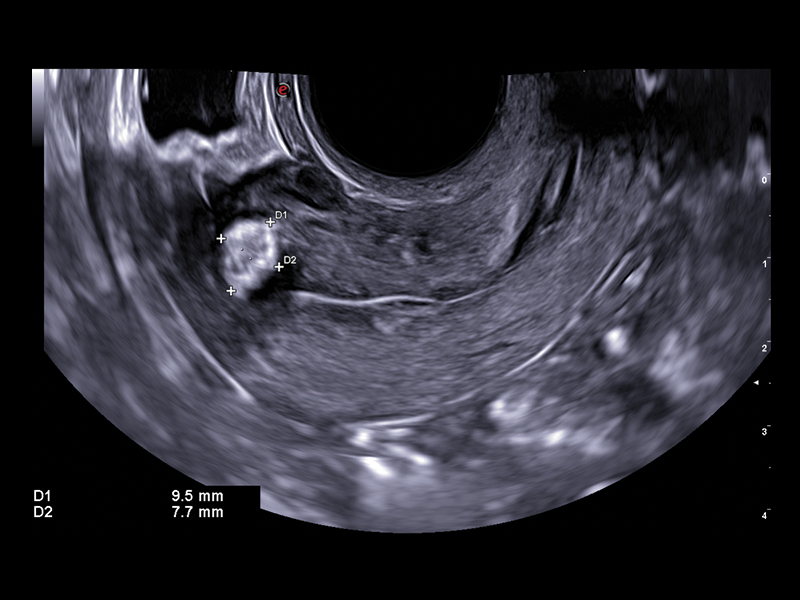

Esaote’s selection of probes for gynaecology provides high-quality images with outstanding contrast resolution, thus increasing clinical confidence in detecting abnormalities and pathologies in the female reproductive system, in both the transabdominal and transvaginal approaches.

The latest micro-convex end-fire transducer, E 3-12, has been designed by the Esaote Probe Centre of Excellence in Florence, with a short convergence radius for maximum resolution, and high capabilities of penetration while preserving the comfort your patient deserves.

The improved vascular image quality together with the extreme sensitivity of Esaote Doppler technologies (Power Doppler and microV) allow the detection of tiny vessels, to precisely assess the extent of the vascularization, to provide you with a better understanding of certain pelvic abnormalities such as fibroids, polyps, or endometriosis conditions.